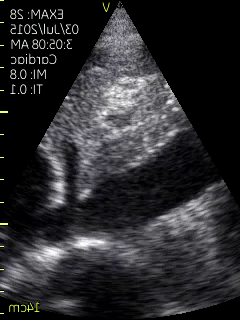

What is this organs? (Black hypoechoic)

Image:

660a4f41-f65a-4d42-b412-bf7315ce7ccc (image/png)

IVC

Aorta